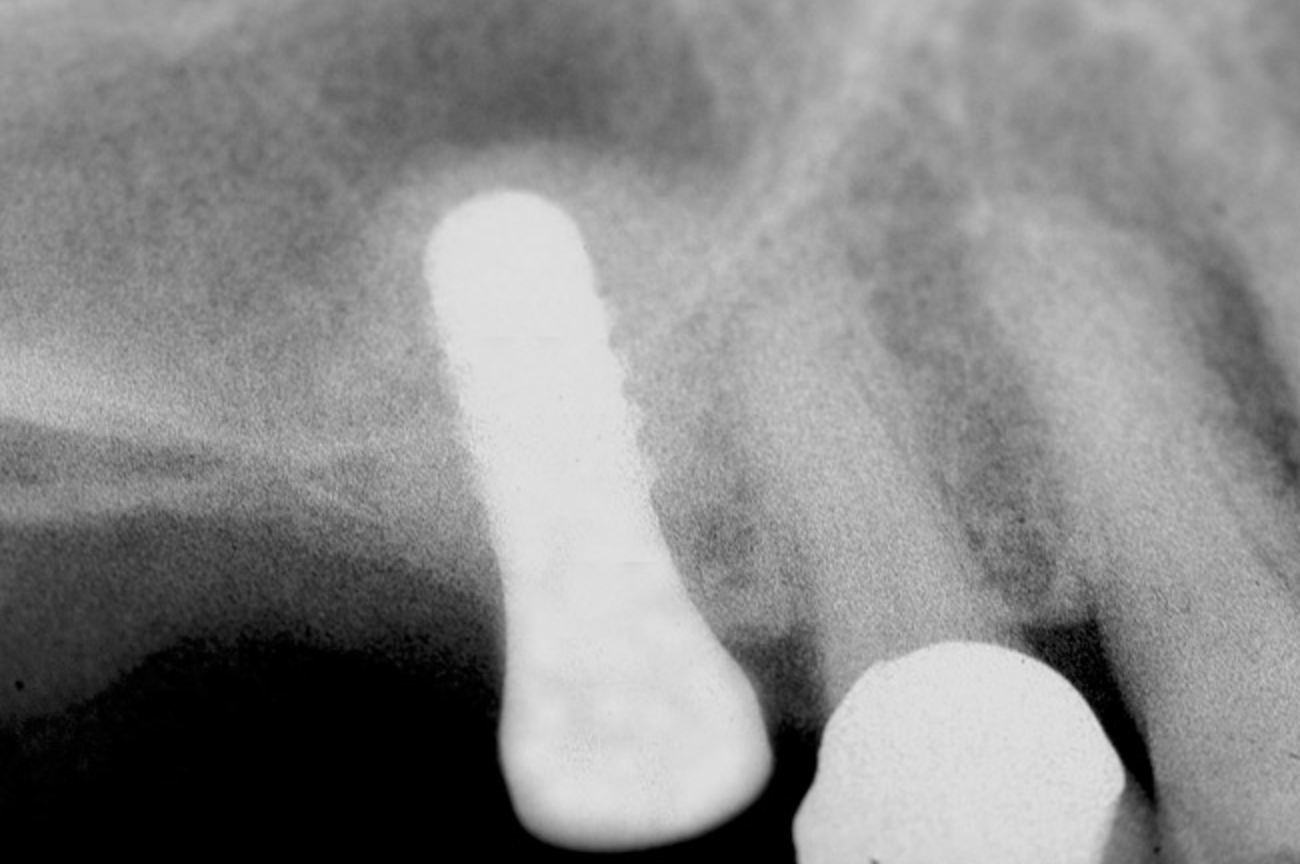

After penetration into the sinus is achieved, a sterile amalgam carrier is used two times to deliver a radiopaque bone substitute into the osteotomy. Then the osteotome used to infracture the subantral floor is lubricated with saline and inserted into the osteotomy until the stop on the osteotome reaches the alveolar crest. This pushes the bone substitute up under the sinus membrane and elevates it. Two more carriers of bone substitute are delivered in the same manner. This will provide around 2 mm of bone height in the sinus (four carriers provide around 2 mm of bone height). A radiograph is then taken to verify that the membrane was elevated, and the bone graft should appear as a dome (Figure 4). If the sinus floor has not been penetrated despite the impression that it was, the bone-graft material may have been pushed laterally. If this occurs, there will be no dome on the radiograph, but, rather, increased osseous density on the lateral aspect of the osteotomy. If this occurs the osteotomy needs to be deepened.

Figure 4  After infracturing the subantral wall with a 3.5-mm osteotome, bone was added and the presence of a dome was confirmed with a radiograph.

Figure 4